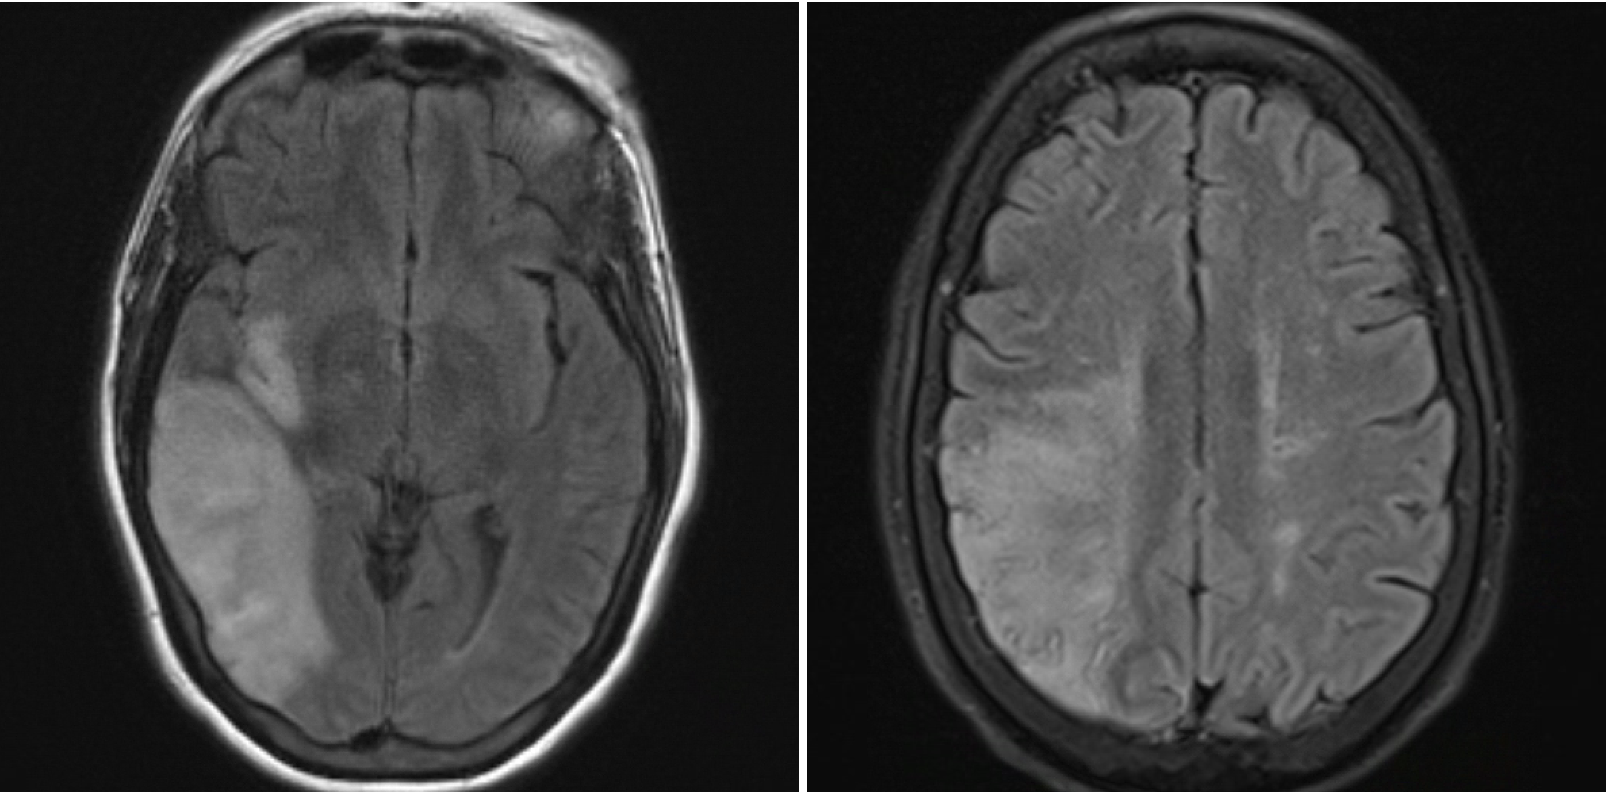

Results: A 59-year-old woman with a past medical history of hypertension, hyperlipidemia, atrial fibrillation, and endocarditis presented to the hospital due to sudden-onset left-sided weakness. A brain MRI showed a right middle cerebral artery stroke. A month after this, the patient returned to the hospital for abnormal movements of her left face and concern for possible focal status epilepticus. An EEG did not report any epileptiform activity. On exam, the patient had left-sided upper motor neuron weakness involving her face, arm, and leg. She was able to raise her eyebrows and close her eyes symmetrically. With closer observation, it was noted that the left side of her mouth would activate every time the patient blinked, consistent with synkinesis. There were no signs of hemifacial spasm. The patient and her family members denied any history of facial nerve involvement before the stroke. Her brain MRI was reviewed, and there was no pathology involving her brainstem. An EMG surveying the bilateral nasalis, orbicularis oculi, and orbicularis oris muscles showed normal amplitudes. Bilateral trigeminal blink responses showed symmetric R1 latencies, findings not suggestive of left-sided facial neuropathy.

Figure 1. Brain MRI